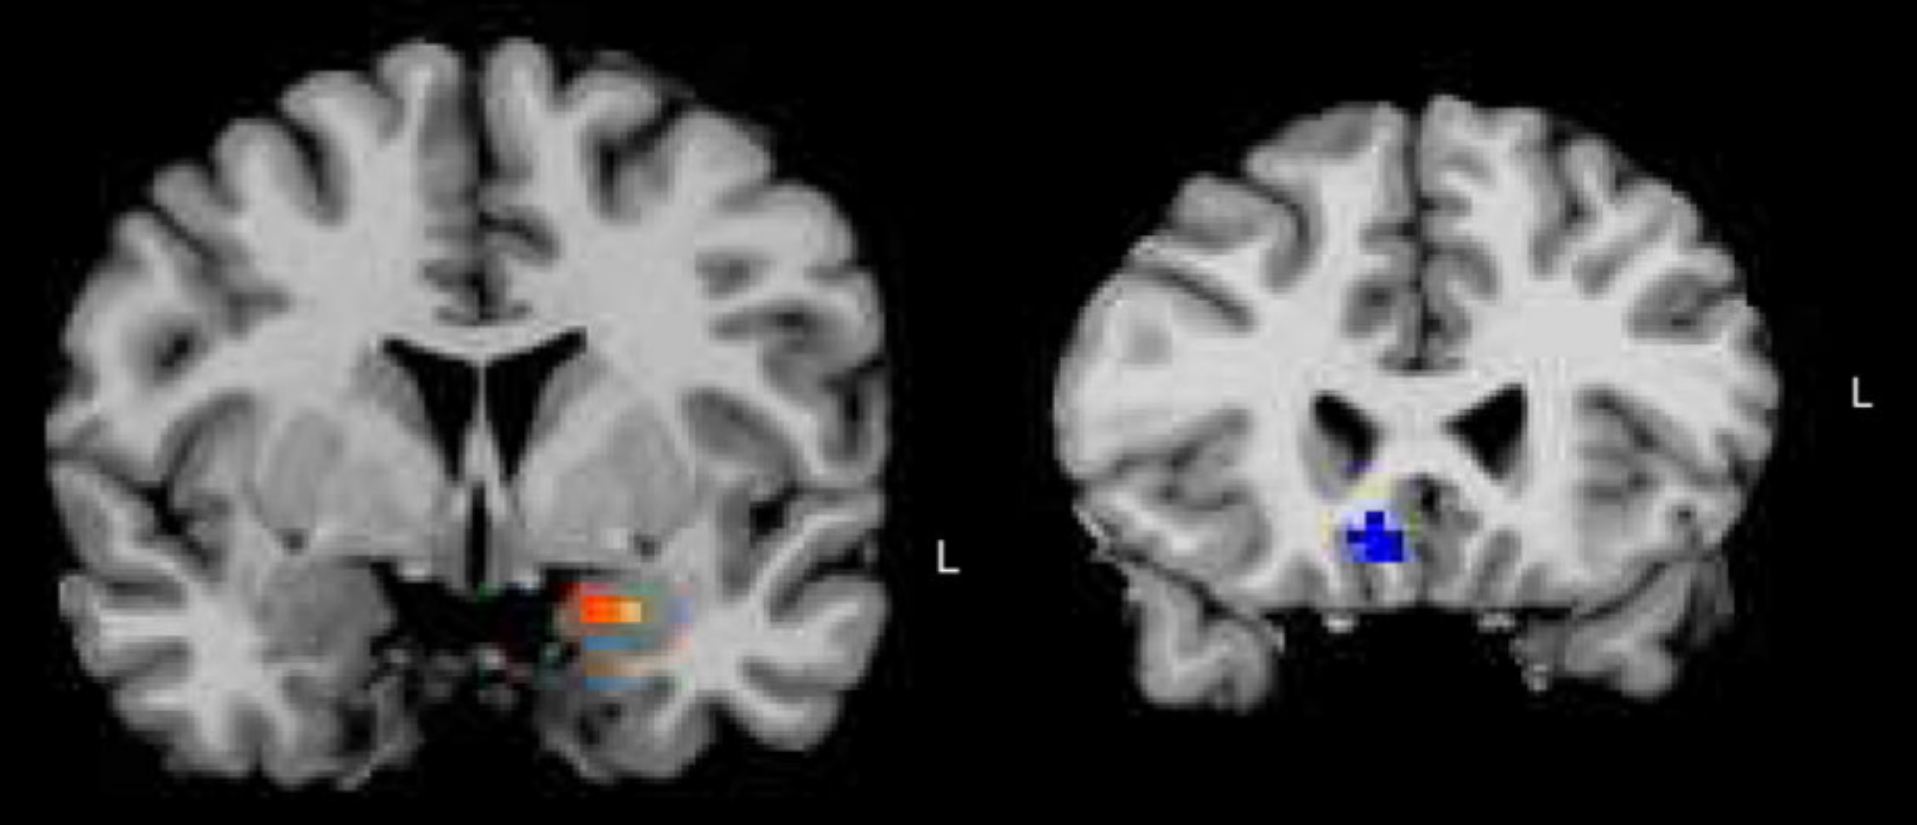

Computational Modeling of Neural Networks

Computational analysis of how depression alters neural responses to emotional music.